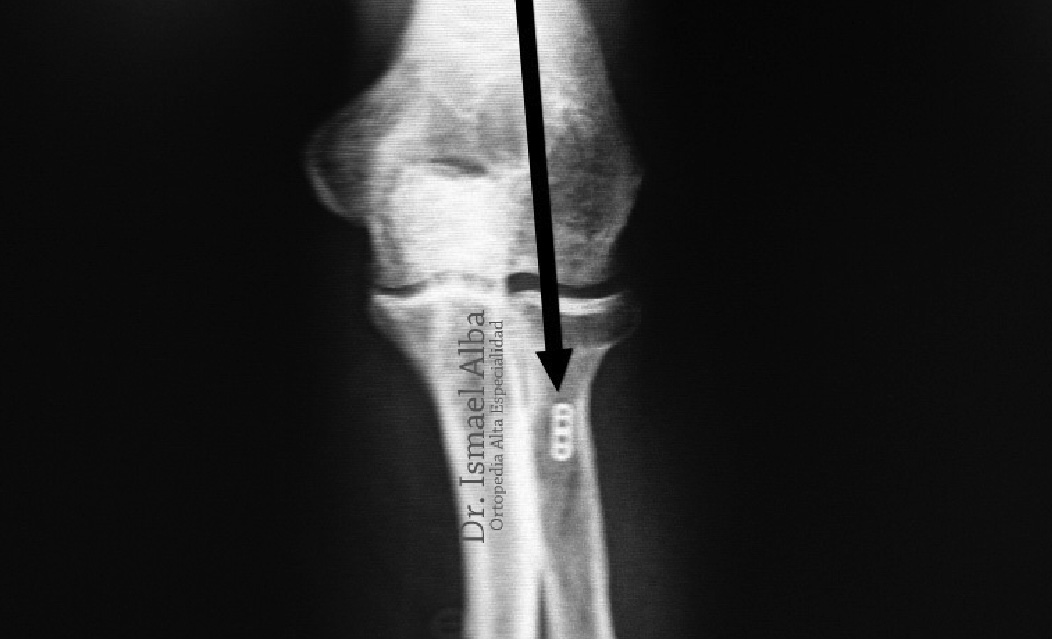

Estudio de imagen

Los estudios de gabinete en los cuales podemos apoyarnos es el ultrasonido y/o la resonancia magnética nuclear. Las radiografías tienen poco uso y se reservan para aquellos pacientes que se sospecha de una lesión asociada como una fractura, luxación o inestabilidad del hombro.